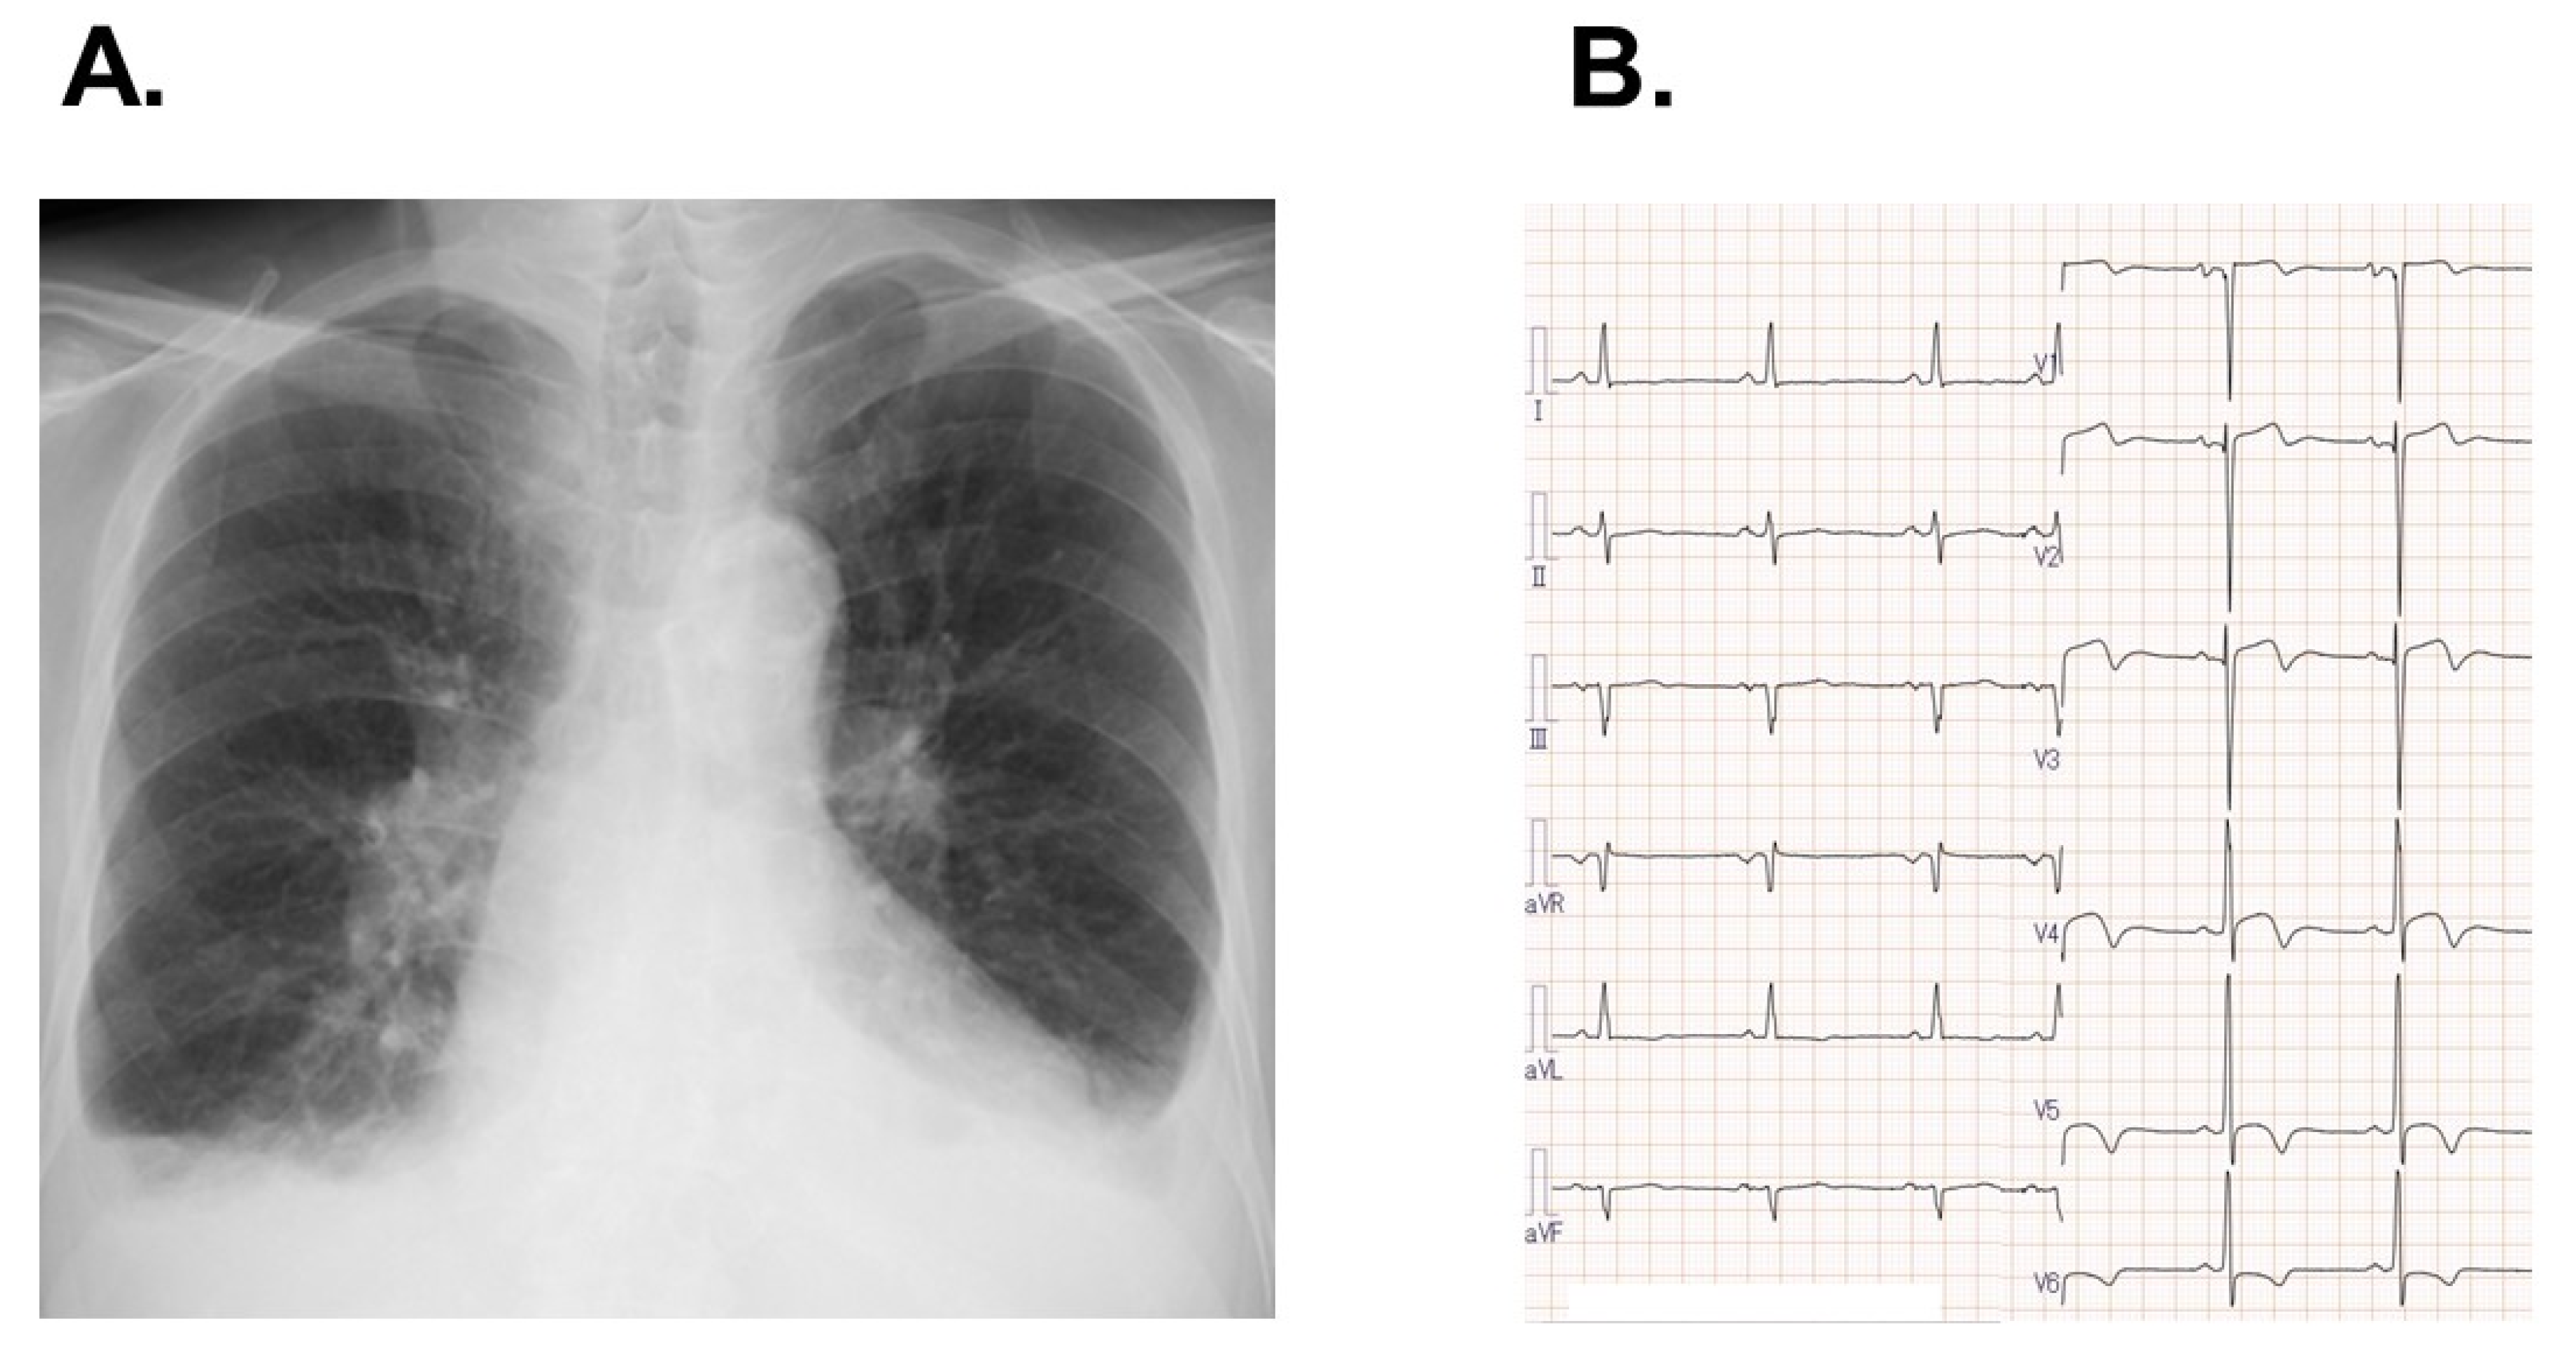

Transthoracic echocardiography revealed a left ventricular end-diastolic diameter of 44 mm and a left ventricular ejection fraction of 25% (Figure 2A). Maximum velocity in the aortic valve was 3.6 m/s, the estimated aortic valve area was 0.52 cm2, and the stroke volume index was 31 mL/m2. There was mild grade aortic regurgitation, mitral regurgitation, and tricuspid regurgitation. A dobutamine loading test demonstrated an incremental maximum velocity in the aortic valve from 3.37 m/s to 4.12 m/s, an incremental left ventricular ejection fraction from 31% to 40%, and the remaining aortic valve area from 0.77 cm2 to 0.66 cm2. Taken all together, the patient was diagnosed with low-flow low-gradient aortic stenosis.

Three months later, the patient was again transferred to our institute to receive scheduled TAVR. On admission, his blood pressure was 146/68 mmHg and his pulse rate was 62 bpm. Left ventricular ejection fraction had improved from 25% to 36% (Figure 2B).

Figure 2. Transthoracic echocardiography (long-axis view) at diastolic/systolic phase on admission expressing left ventricular ejection fraction of 25% (A) and those following 3-month medical therapy showing left ventricular ejection fraction of 36% (B).